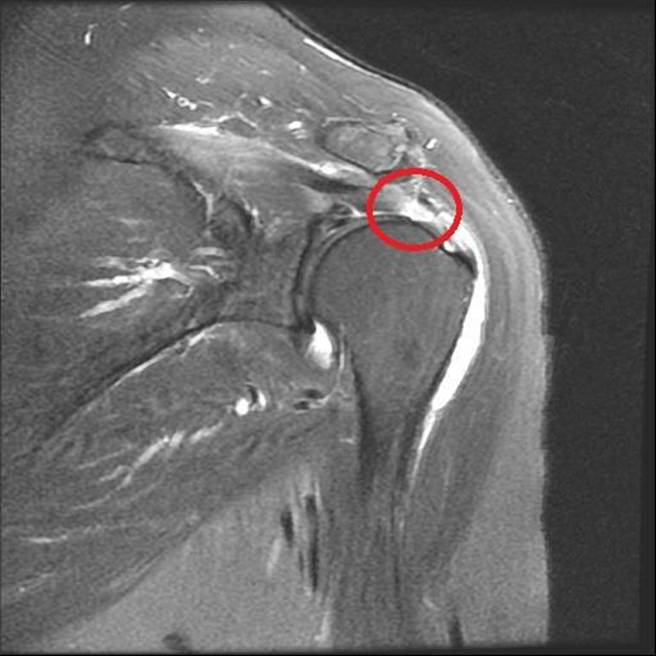

苏皇儒指出,旋转肌肌腱这类软组织损伤,会先透过超音波和核磁共振等影像学检查,分为全层破裂或部分破裂,状况较轻微者,可考虑口服药及局部关节注射,配合復健物理治疗2至3个月后,评估病人症状给予治疗上的调整。

苏皇儒说,以「阿伟师」为例,医疗团队透过微创关节镜手术缝补撕裂的旋转肌肌腱,在肩关节周围开4到5个仅0.5公分的小伤口清除发炎的组织,减轻疼痛,并在关节镜辅助下,使用铆钉缝补撕裂受伤的肌腱,配合术后復健,患者仅1个月左右症状明显改善,3个月后顺利恢復下厨做菜。